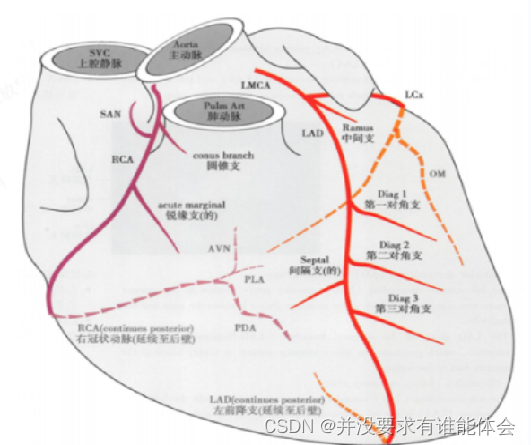

冠脉解剖-起源

冠状动脉通常起源于主动脉冠状动脉窦,右冠状动脉起源于右冠状窦(位于前方),左冠状动脉干起源于左冠状窦(左后方)

无冠状窦:(右后方)

冠脉解剖-优势性

根据后降支和左室后支供应左心室后壁决定优势型,将冠状动脉分为以下3型:

1.右冠优於型:大约占85% 左右,后降支和左室后支起自右冠状动脉;左冠仅达左心室侧缘的左心室后壁

2.均街型:可见于7%病例,通常右元脉供应后降支,回旋支供应左室后支

3.左冠优势型:约8%病例,左旋支达右心室后壁,后降支和左室后支起自左回旋支,而冠仅达右心室右侧缘的右心室后壁

冠脉解剖-走形、分段

右冠状动脉:白右冠状赛发出后,行走于主肺动脉干和开主动脉根部间的右房室沟内,绕向心胜右后方再向左后走行,沿途发出圆锥支、实房结支、說缘支、后降支

圆锥支:第一分支,发自右冠状动脉最近端,供应右室的肺动脉圆锥。30%左右从主动脉发出;

实房结支:60%起自右冠状动脉,40%起自左冠状动脉;

税缘支:供应右心室前壁;

右后降支供应左心室下壁和房室结。

左冠状动脉主干:主要分为左前降支和左回旋支,直径分别为5-10mm和4-5mm。部分还发出中间支。

左前降支:由左冠状动脉主干向前下沿前室间沟行走于左、右心室间,远抵心尖部,在78%的心脏中折向心脏膈面的后室间沟与后降支吻合。主要向左心室游离壁、室间隔前上2/3及心尖部供血。沿途发出对角支和前室间隔支

左回旋支:呈近乎直角从左主干发出,沿左房室沟向左后行走至后室间沟。向左室侧壁,后壁供血。沿途发出钝缘支和左房旋支。

冠脉解剖-分段

第1段:右冠近段 (pRCA),右冠开口到锐缘支开口一半长度

第2段:为右冠中段(mRCA),其余到锐缘支开口处另一半的长度

第3段:为右冠远段(dRCA),右冠中段末端-后降支(PDA)开口

第4段:右冠起源后隆支 (R-PDA)

第5段:左冠状动脉主干(LM)

第6段:前降支的近段(mLAD):开口到第一室间隔支的开口

第7段:前降支的中段(mLAD):间隔支的开口到心尖部的-一半长度

第8段:前降支的远段(dLAD):前降支中段末端到前降支未梢

第9段:第一对角支(D)

第10段:第二对角支(D2 )

第11段:回旋支近段 (pLCX),回旋支开口处-钝缘支开口处

第12段:第一钝缘支 (OM1)

第13段:回旋支远段(dICX):钝缘支开口以远部分

第14段:第二钝缘支 (OM2)

第15段:回旋支发出的后降支 (L-PDA)

第16段:右冠起源后侧支 (R-PLB)

第17段:中间支(RI):起自LAD和LCX分叉处

第18段:回旋支起源后侧支 (L-PLB),后侧支起源于回旋支